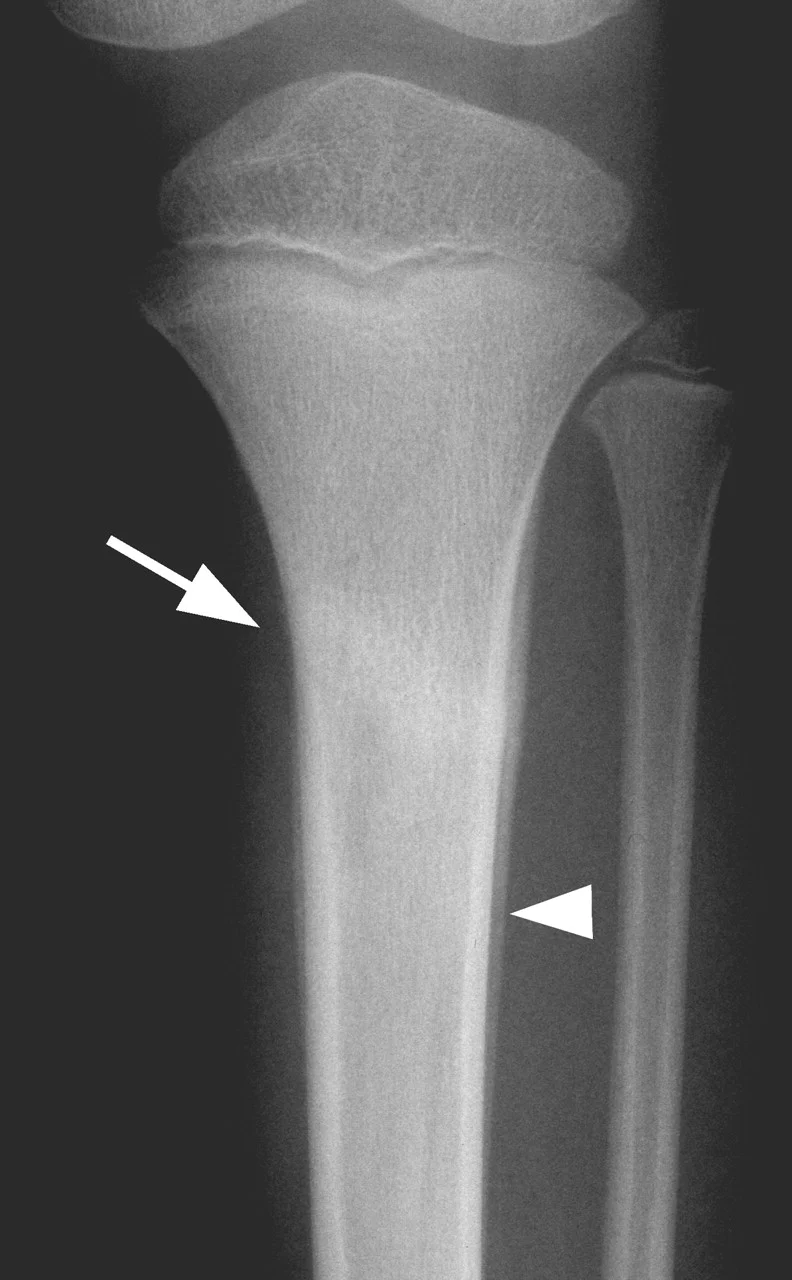

Stress Fractures

- Bone reacts to repeated loading, may become fatigued & a crack develops

- Fatigue fractures

- Abnormal stress or torque on a bone that has normal elastic resistance

Stress Fracture Details

- Usually Transvers

- 2nd metatarsal

- Tibia

- Fibula